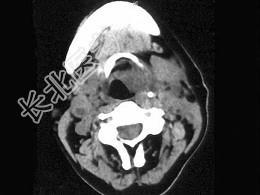

- 单项选择题女,54岁, 鼻咽部异物感约3个月,PE: 左侧声带固定,可见肿物, CT如图所示,应诊断为 ( )

B、喉癌